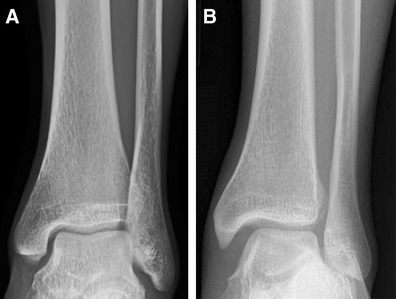

Radiographic evaluation should include weight bearing (where tolerated by the patient) and three views of the ankle joint (anteroposterior, mortise, lateral). Tibia/fibula x-rays should be obtained if there is clinical suspicion of fracture, particularly high in the fibula. In addition to diagnosing fracture and proximal fibula injury, radiographs can be useful in demonstrating disruption of the normal relationship between the distal tibia and distal fibula, which may be indicative of syndesmotic injury. Classically, syndesmotic injuries may be present if radiographs show increased tibiofibular clear space, decreased tibiofibular overlap, and/or increased medial clear space (Fig. 2, Table 1) [19, 20].

Fig. 2.

Anteroposterior radiographs of a normal ankle (a) and an ankle with syndesmotic injury (b). Note the widened medial clear space, loss of tibiofibular overlap, and widening of the distal tibiofibular syndesmosis